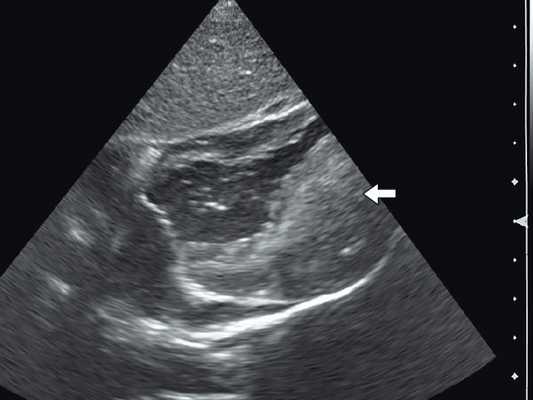

Рис. 3. Эхокардиограмма гигантской рабдомиомы (стрелка) у девочки марфаноидного статуса без признаков туберозного склероза (субксифоидальный доступ).